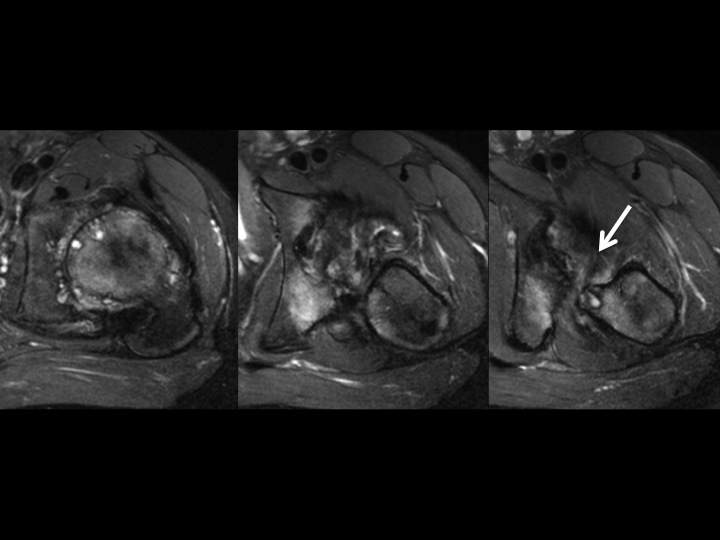

36M with DDH, chronic pain, recent onset more severe pain

I am asking for your thoughts. This is chronic DDH with severe secondary DJD. The femoral head is superiorly migrated with chronic degenerative remodeling of the FH and acetabulum. This brings the posteroinferior acetabular rim and lesser troch into close approximation and appears to cause some sort of impingement. Caudal to that site, there is isolated edema of what is either the Quad Femoris or possibly the Add Magnus (I am confused by the anatomic distortion), which cannot be due to direct muscle friction. I do not know if the Acetabular-Less Troch friction is the direct cause of symptoms, if that is causing nerve impingement, or if there is a muscle strain due to the abnormal stress of the deformity (seems least likely as the deformity is chronic). Please help.

acetabular-femoral impingement